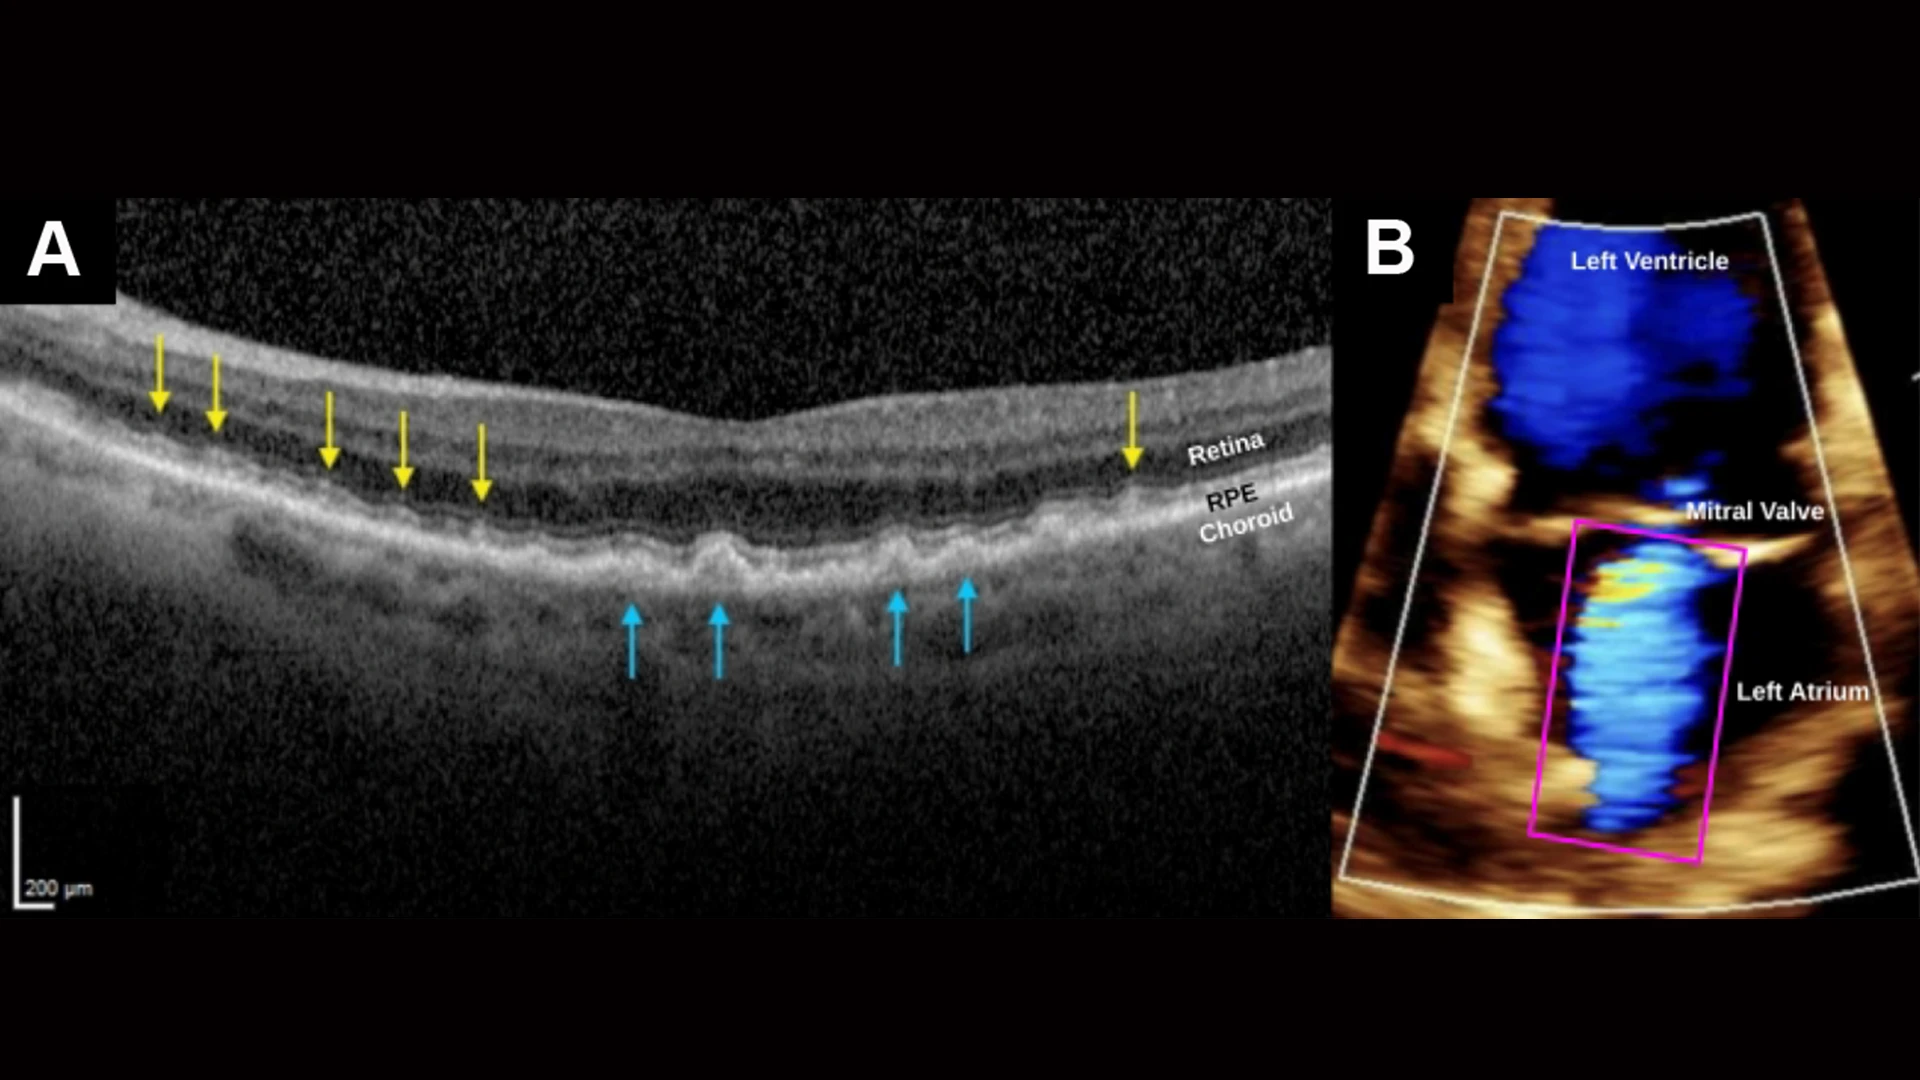

SDDs caused by severe cardiac valve disease. (A) SD-OCT scan, right eye, shows myriad SDDs (yellow arrows) above the RPE and several drusen (blue arrows) beneath the RPE in a patient with severe mitral valve regurgitation and compromised cardiac output. The insufficient ocular perfusion downstream then results in the SDDs. The left eye was similar. (B) A color doppler transthoracic echocardiogram of the left ventricle during systole, showing markedly reduced cardiac index, 1.87 L/min/m2, normal range 2.5-4.0, and severe mitral valve regurgitation. Left atrium shows turbid jet of arterial blood flowing retrograde from the left ventricle.